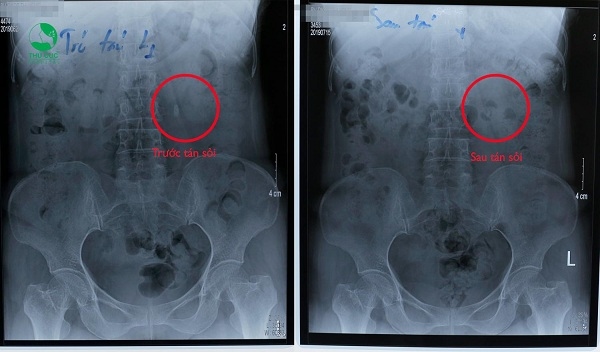

Kết quả tán sỏi ngoài cơ thể, sỏi mềm chỉ cần tán 1 lần là sạch.

Tán sỏi ngoài cơ thể rất hiệu quả cho các trường hợp sỏi thận 1.5cm. Chia sẻ tới các bạn một trường hợp có sỏi thận 1cm uống thuốc nhiều năm không hết được điều trị bằng phương pháp tán sỏi ngoài cơ thể.